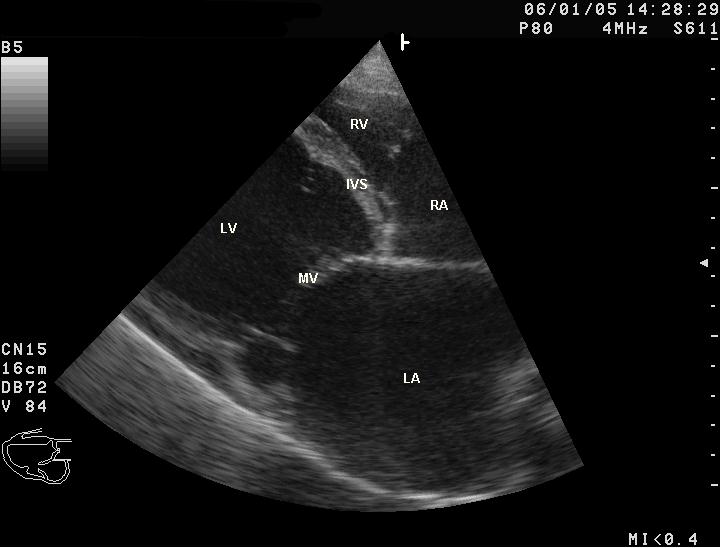

3) 심초음파

- 좌심실 확장, 좌심실 수축기능 저하, 심실중격 두께는 정상, 승모판 역류